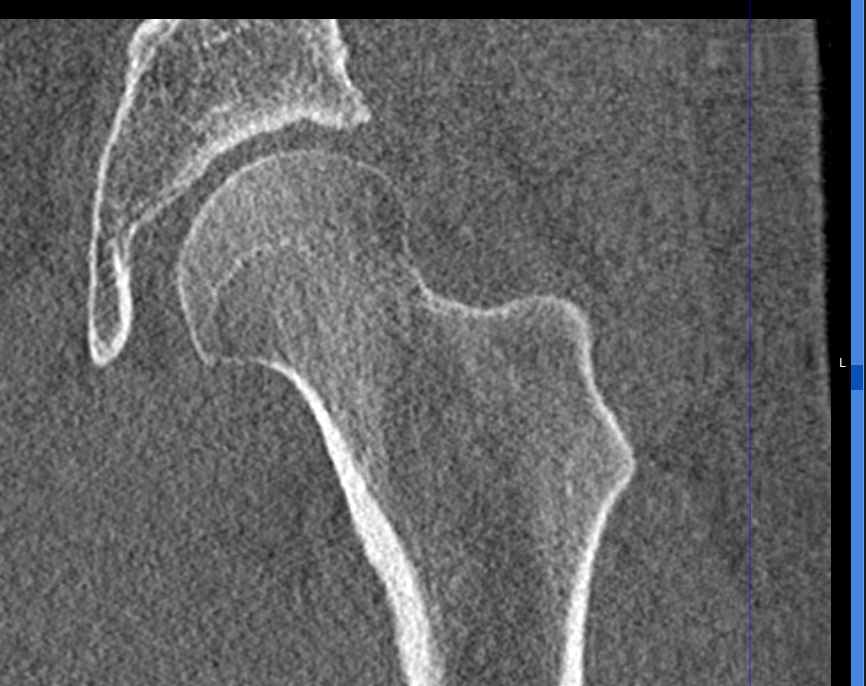

КТ относится к лучевым методам исследования, то есть предусматривает использование рентгеновского излучения, которое хорошо поглощается костной тканью. В результате сканирования и последующей цифровой обработки полученных данных получаются подробные снимки в различных плоскостях, а также трехмерные изображения тазобедренных суставов, позволяющие оценить пространственное расположение суставных поверхностей, внутрисуставных структур и окружающих тканей.

Снимки высокого разрешения позволяют выявить минимальные изменения в костных структурах и окружающих тканях. Мультиспиральная КТ может применяться в экстренных ситуациях для диагностики травматических повреждений тазобедренных суставов, в частности, при переломах шейки бедра. Кроме того, исследование незаменимо при планировании оперативного вмешательства, а также в послеоперационном периоде для оценки успешности проведенной операции и для отслеживания процесса восстановления.

Что показывает КТ тазобедренного сустава

- повреждения костной ткани (перелом головки, шейки бедра, вертлужной впадины);

- перелом шейки бедра;